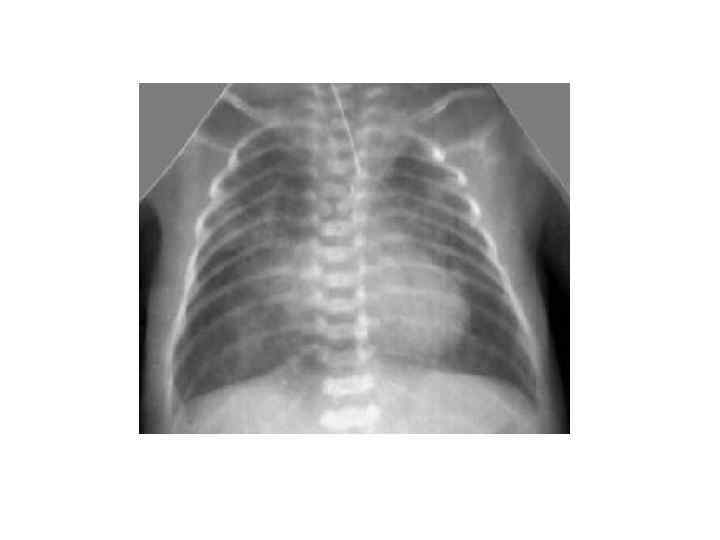

Сегментарные и полисегментарные ателектазы (3 -5 дн) § У относительно зрелых новорожденных § Тяжелое или среднетяжелое течение респираторных нарушений § Способствуют: аспирация, ВЧК, спинальные травмы, передозировка седативных препаратов в родах § Клиника: - ДН с рождения - цианоз постоянный - перкуторно – укорочение перкуторного звука - аускультация – ослабленное дыхание на стороне поражения § Рентгенологически: диффузная гомогенная тень, на фоне которой не виден легочный рисунок, м. б. смещение средостения в больную сторону